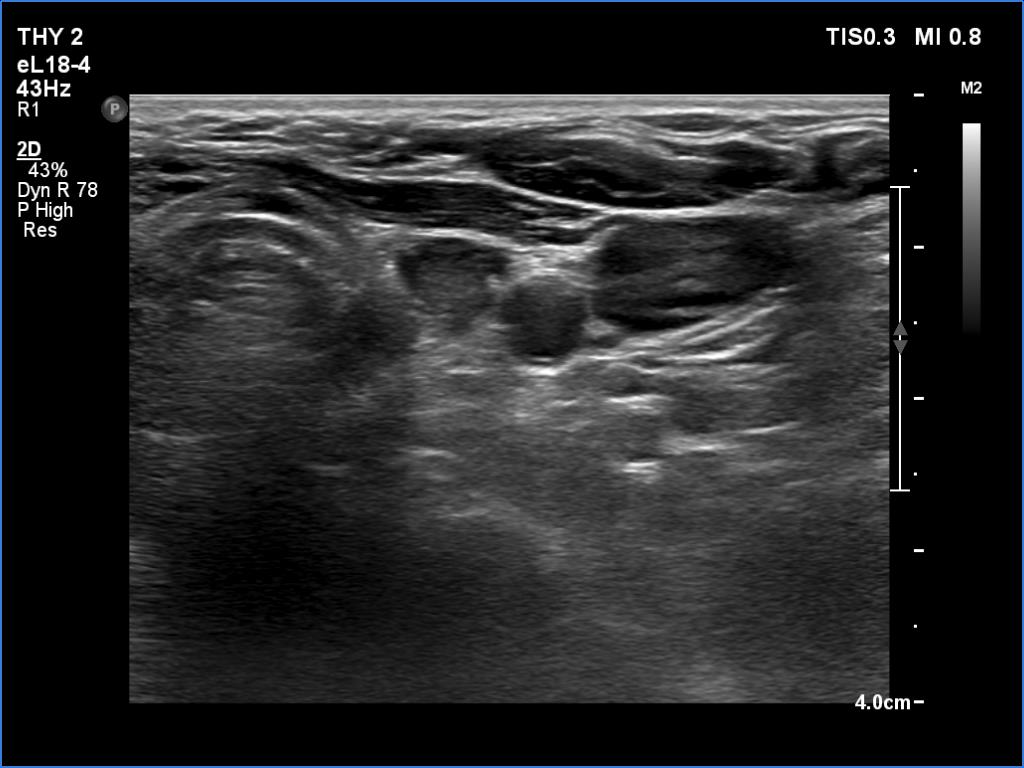

Introduction - case 162 (ultrasonographic picture 3)

Left lobe, transverse view - with less harmonic settings. There is a hypoechoic mass in the left throid bed. On this view, this could be even a normal finding.